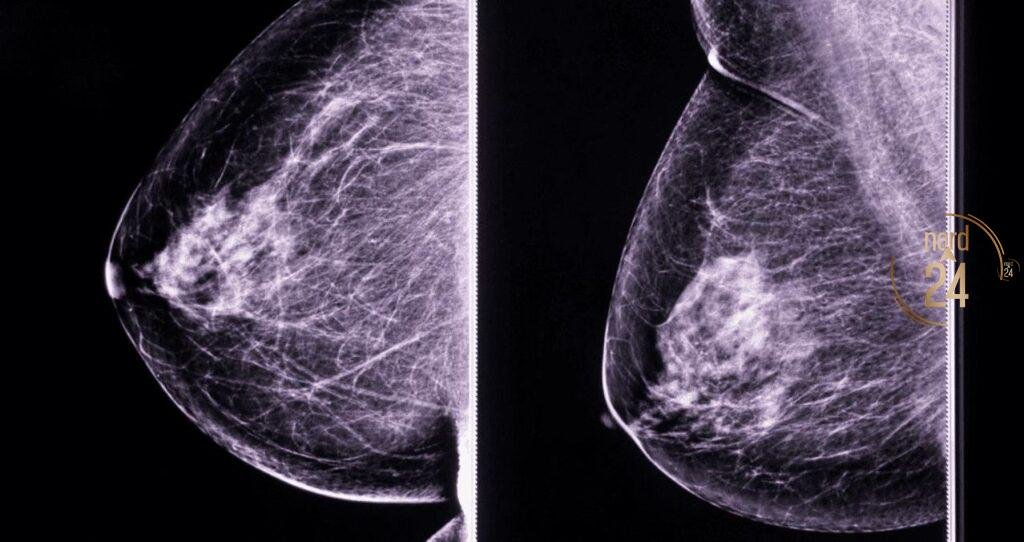

Liliana Velozo, una vecina de 53 años, compartió su valiente testimonio en Radionord tras haber atravesado una cirugía radical de mama derecha hace cinco meses. Durante la entrevista con María Mercedes y su equipo, la paciente detalló los desafíos que enfrenta en su proceso de rehabilitación postoperatoria. Aunque el camino ha sido complejo, Liliana destacó la excelente atención humana y profesional que recibe en el nuevo Instituto Oncológico, donde accede a sus controles y medicación de hormonoterapia sin costo alguno.